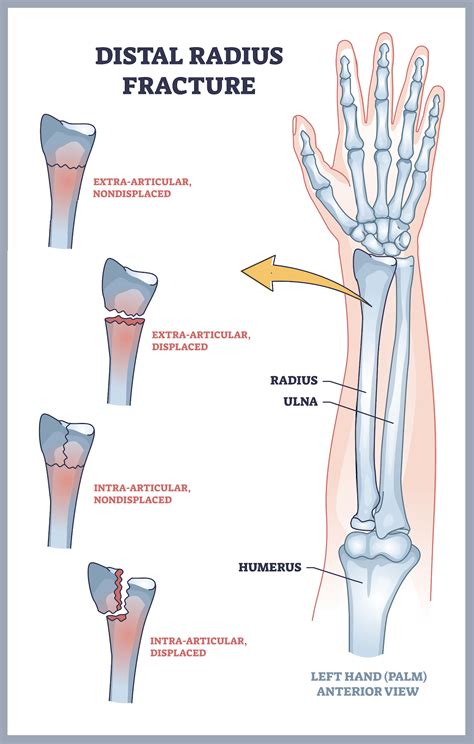

Distal Radius Fracture

Also known as a Colles’ fracture, this is one of the most common Types Of Wrist Breaks. It occurs when the radius bone breaks near the wrist, often due to a fall on an outstretched hand. Symptoms include immediate pain, swelling, and deformity of the wrist.